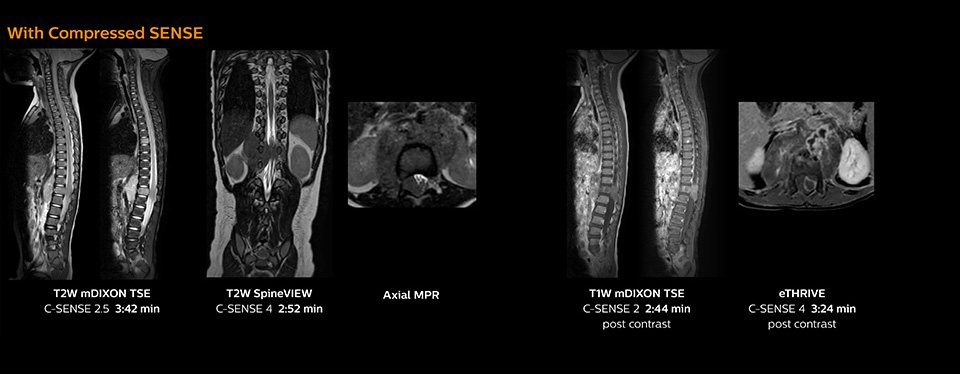

“Previously with SENSE, our 2D mDIXON TSE scans required relatively long scan times. But now, with Compressed SENSE, we have reduced these scan times while maintaining a high SNR, because the Compressed SENSE technology helps reduce noise,” says Dr. Koyama. “Because the faster scanning with Compressed SENSE saves us time, we can sometimes add a sequence to obtain high quality spine images in the same time slot for confident diagnoses. And in cervical spine exams, a 2D sequence is sometimes replaced by a 3D protocol, which provides us more information as it can be reformatted in different orientations. Compressed SENSE allows us to easily add this 3D sequence in the timeslot,” says Fukushima “Incorporating Compressed SENSE in common spine sequences, such as mDIXON, 3D SpineVIEW and eTHRIVE, can substantially reduce the scanning time of these sequences, while maintaining adequate spatial resolution, resulting in high quality, multiple contrasts, multiple orientations,” says Dr. Koyama. “In addition, fast sequences generally make it easier for patients to stay motionless throughout the scans, so it also helps us in that way.”

This 6-year-old patient with neuroblastoma underwent MRI on the Ingenia 1.5T. Compressed SENSE was used to reduce scan time while maintaining the high resolution for 2D mDIXON, 3D SpineVIEW and e-THRIVE in this case. The highly detailed images allowed the radiologist to make a quick and confident assessment of the position of the nerve and the tumor. Especially important for a pediatric patient, is that a shorter scan time also allows us to keep the sedation time as short as possible.

As this was one of the first patients scanned with Compressed SENSE, 3D SpineVIEW was acquired with and without Compressed SENSE to allow comparison. Although the Compressed SENSE sequence was significantly faster, the acquired and reconstructed 3D SpineVIEW images show virtually the same image quality.